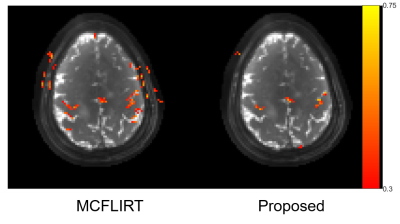

Fig. 2 shows the results of the phantom experiment. Compared with MCFLIRT, our method effectively reduced the blurring caused by the intra-frame motion. Fig. 3 displays the in-vivo reconstruction results, where the proposed method reduced blurring. Fig. 4 shows activation maps calculated from MCFLIRT and the proposed method. MCFLIRT falsely showed activation in the skull due to motion, whereas the proposed method accurately reflected voxels in the motor cortex.

Figure 4. Activation maps for the two motion correction methods. MCFLIRT led to scattered false positives due to motion, while the proposed iterative method reflected accurate correlations of the motor cortex.